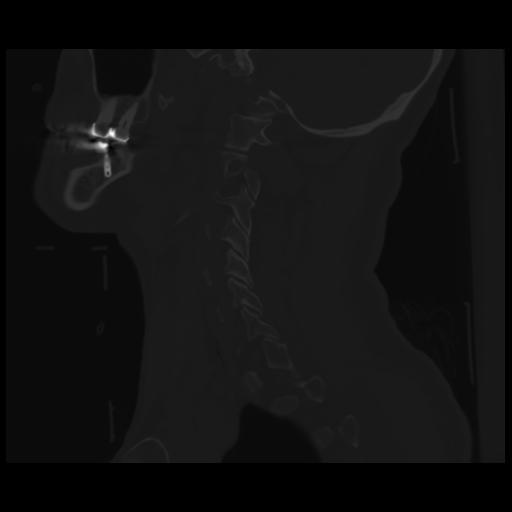

14 P.BLANDAS,,Sagittal,2.000,P.BLANDAS,Sagittal,